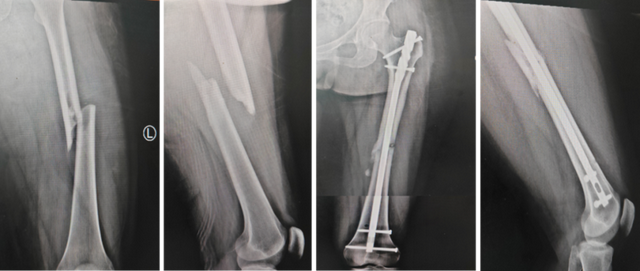

胫骨干骨折髓内钉固定

胫腓骨多端骨折胫骨髓内钉+腓骨弹性髓内钉固定